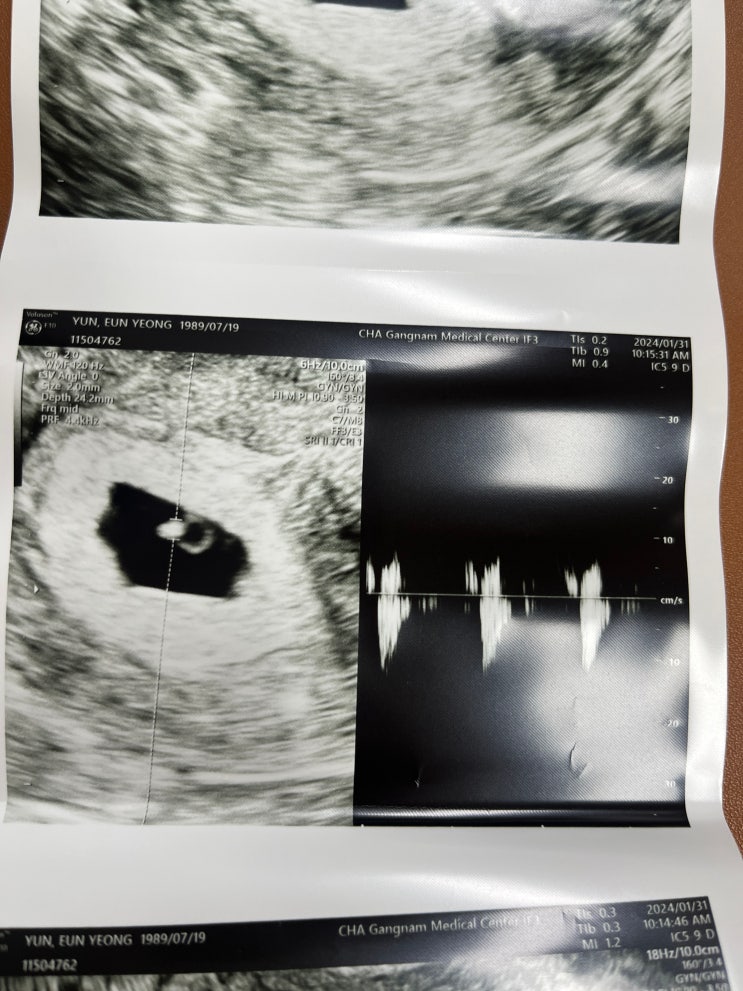

[5w,5d] 다이아몬드 링 발견, 뜻밖에 심장소리

갈색혈이 토요일부터 보였다. 월요일이 되니 거의 보이지 않아서 괜찮아지겠지 했지만 .. 수요일에 갑자기 ...